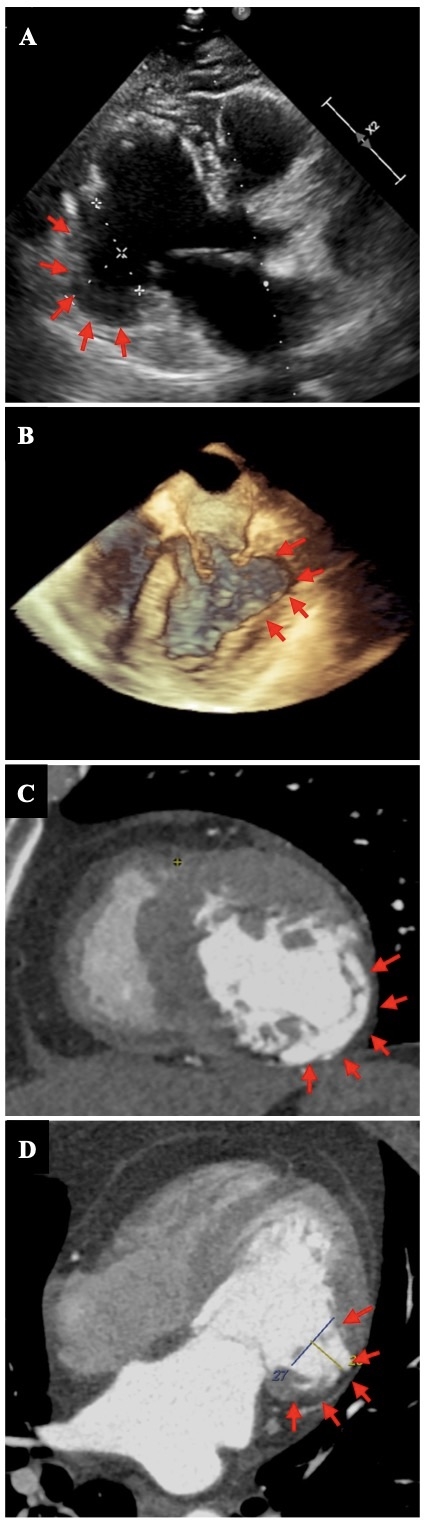

Case Presentation: A 59-year-old woman from southern Peru presented to the ED with palpitations and dyspnea for 1 week. Physical exam was normal. ECG showed Q waves in III and AVF leads. TTE revealed an LVEF of 45% with an inferolateral LV aneurysm. Coronary angiography showed no lesions. CCC was suspected and serology was ordered, which was positive for T. cruzi. Cardiac MRI confirmed the presence of a 32x22mm basal inferolateral LV aneurysm. During hospitalization, she experienced 4 episodes of unstable monomorphic ventricular tachycardia (VT) within 24 hours, requiring defibrillation with 200J, vasopressor support, and invasive mechanical ventilation. The diagnosis of electrical storm secondary to CCC was proposed, for which amiodarone infusion was started until complete impregnation was achieved. Additionally, support was provided with IABP and specific antiparasitic treatment with benznidazole. Electrophysiology determined that the probable focus of the VT was situated at the level of the LV aneurysm. Therefore, ablation with endocardial-epicardial mapping was performed. However, the patient continued to experience recurrent episodes of VT. Consequently, in a multidisciplinary discussion, it was decided to perform a ventricular aneurysmectomy, which was successful. The patient's clinical progress was favorable, with initiation of GDMT and placement of a single-chamber ICD for secondary prevention. After one year of outpatient follow-up, the patient remains free of VT recurrences. Conclusion: Ventricular aneurysmectomy is a successful management approach for patients with CCC who present with electrical storm refractory to antiarrhythmic drugs and catheter ablation, and whose VT is believed to originate from the aneurysm. The diagnosis of CCC is highly arrhythmogenic and should be suspected at an early stage, given the patient's demographics and the presence of LV aneurysm in the absence of coronary artery disease.